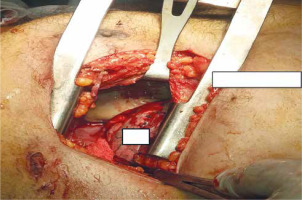

Figure 2

Chest CT view. A – Transversal views of chest CT scan with mediastinal, right pleural extension of mediastinal infection. B – Transversal views of chest CT scan with mediastinal, and bilateral pleural extension of mediastinal infection (arrows)